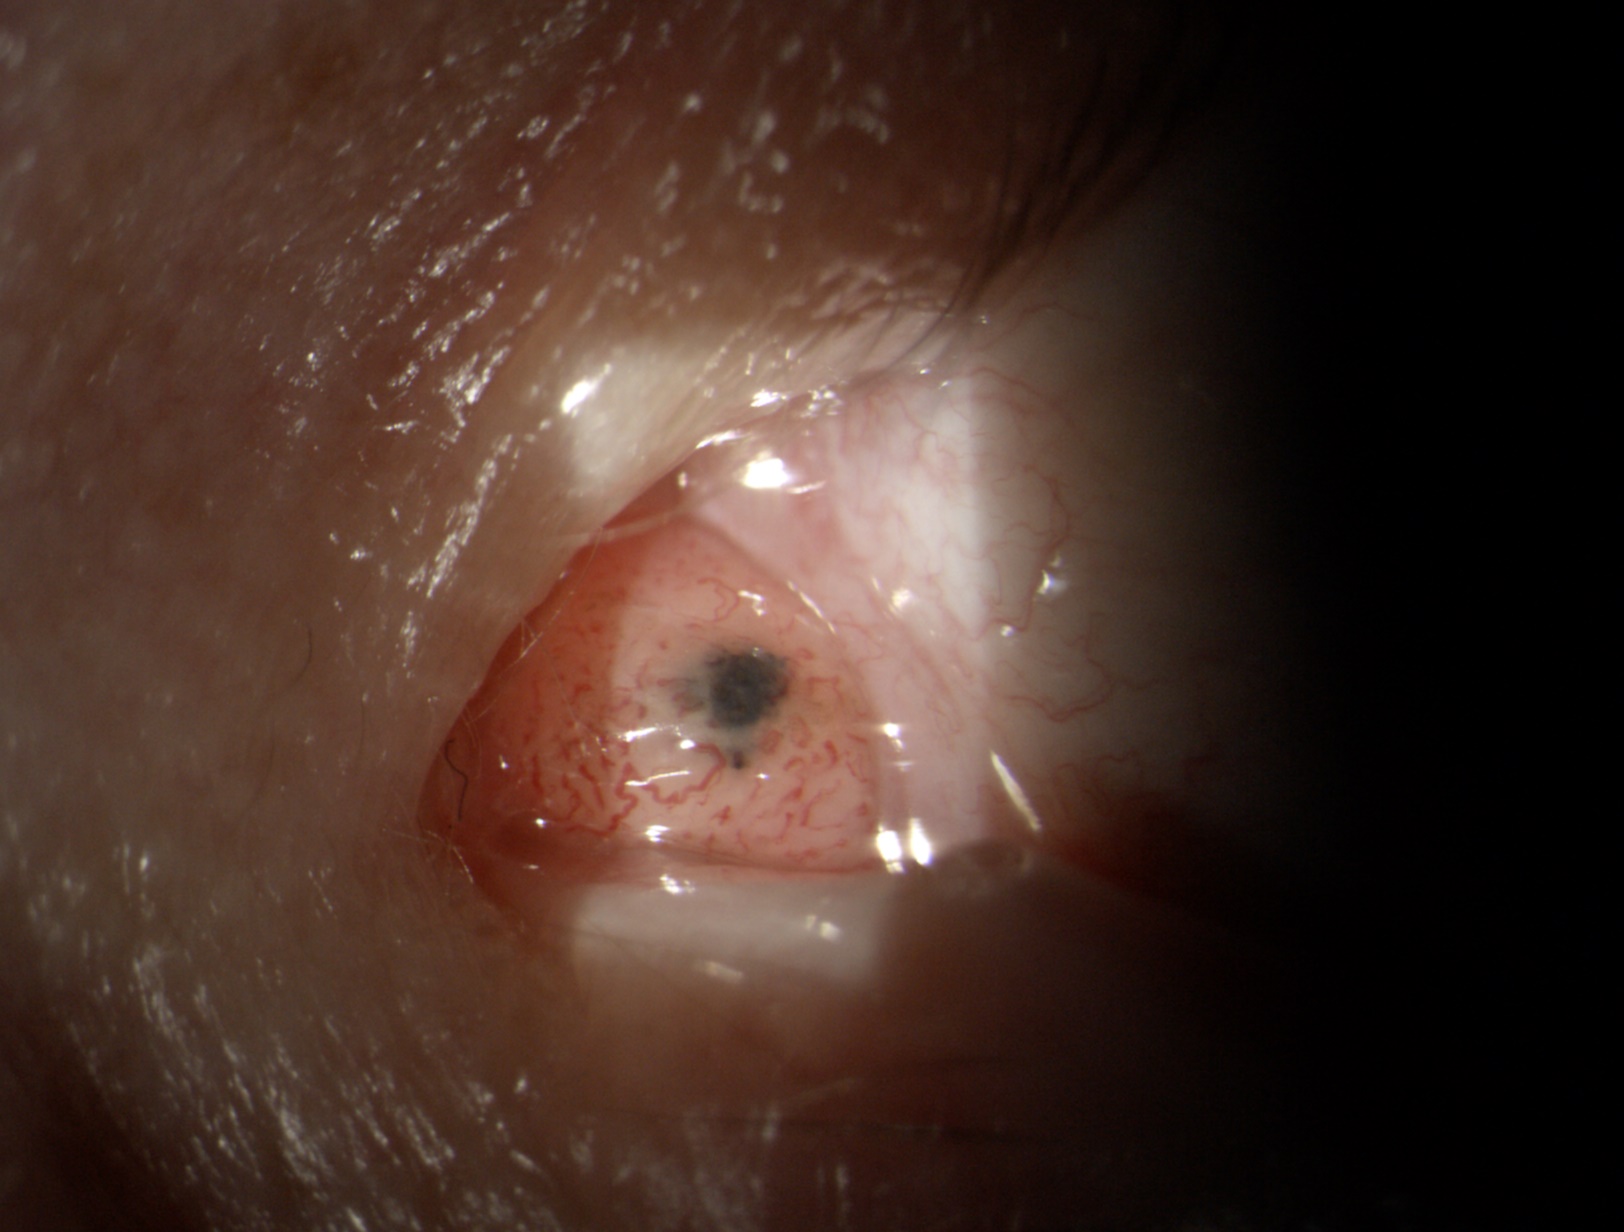

Jeder Augenarzt und jede Augenärztin kennt solche Beispiele aus der Praxis: Ein Patient kommt mit einem Bindehauttumor in die Praxis. Das kann ein harmloser Nävus sein – eine gutartige Fehlbildung wie es auch ein Muttermal ist (Abbildungen 1 und 2). Es kann aber auch ein bösartiger Tumor sein. Deshalb gilt es genau hinzuschauen und den Verlauf zu beobachten: Verändert er sich von einer Untersuchung zur nächsten? Dies lässt sich jedoch ohne eine Fotografie nicht dokumentieren. Ein anderes Beispiel ist das Netzhautscreening bei Menschen mit Diabetes: Sie sollen regelmäßig augenärztlich untersucht werden, um bei Schäden an der Netzhaut rechtzeitig reagieren zu können. Auch hier ist es unerlässlich, bei jeder Untersuchung Fotos der Netzhaut anzufertigen, um Veränderungen im Detail nachvollziehen zu können (Abbildungen 3 und 4).